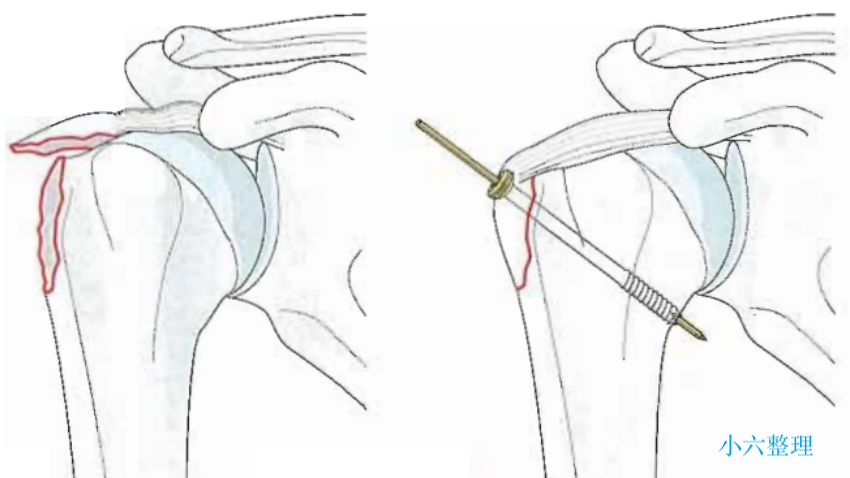

Park 等认为对于运动员或需要手臂过头的体力劳动者,大结节骨块发生 0.3 cm 的移位也应当手术复位;

单纯大结节骨折移位较大甚至突入肱骨头及肩峰之间。

目前常用的外科技术